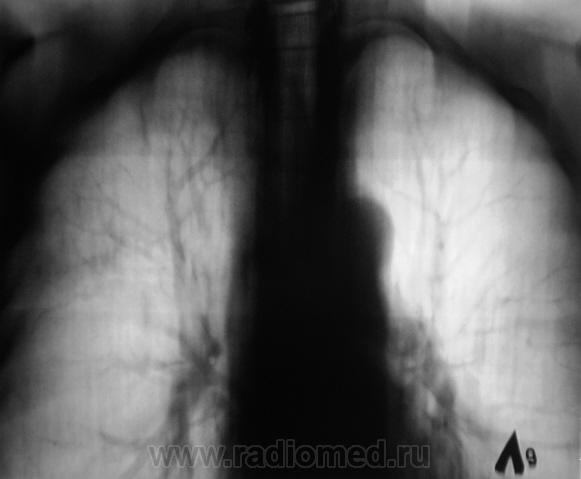

Произведена рентгенограмма в прямой стандартной проекции и томограммы в стандартных срезах.

«Пневмония», сразу показалась какой-то «фердиперсовой», с учетом лечения в стационаре ранее, довольно хорошего самочувствия пациента и наличием весьма «убогой» клиники. После проведения исследования было рекомендовано провести противовоспалительное лечение, исследование мокроты с целью проведения дифференциальной диагностики, рекомендована консультация фтизиатра.

Пациента добросовестно «пользовали» в течение 2 недель, затем был направлен на рентген-контроль.

Мы в протоколе, конечно, отметили, о возможности инфильтративного туберкулёза, д/д ряд даже не дали.

Коллега фтизиатр кричит, что «это не мое», говорит об определенной динамике по рентгенограммам и томограммам, опирается на наличие воздуха в бронхах (воздушная бронхограмма), гнет линию в сторону пневмонии. Да, его коллегу, тоже можно понять, ибо, давно «план» по выявлению выполнили и даже перевыполнили, его тоже, по всей видимости, за выход за «рамки плана» по голове -то не погладят.

Но, мы стойко несмотря ни на что, стояли на тубере.